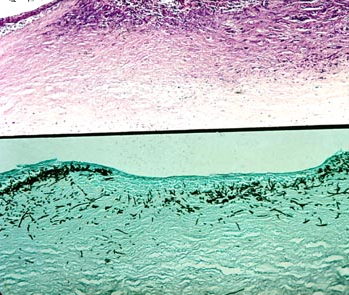

霉菌性角膜溃疡